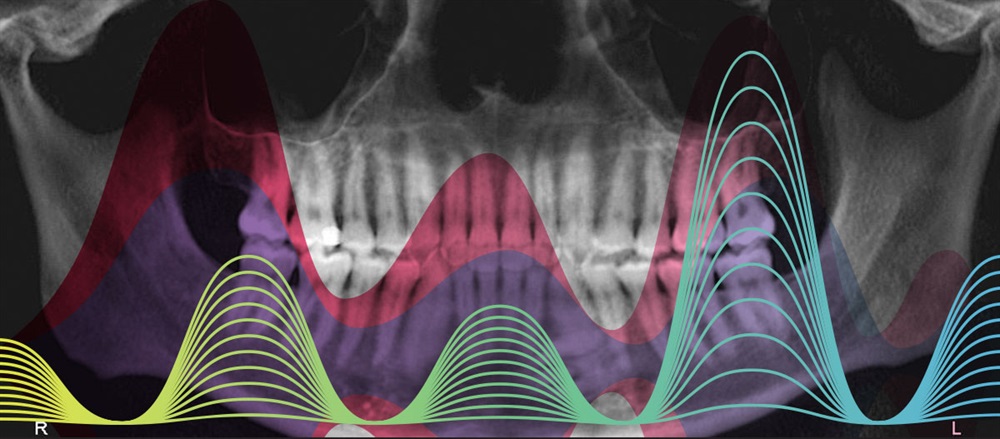

If you look at the patient’s initial panoramic radiograph (Fig. 1), another “fun fact” is that interesting radio-opaque mess overlaying the root of his lower left canine: The patient has three supernumeraries present, which I verified on some cross-section images from our iCat cone beam machine.

Fig. 1: Initial photos and X-rays.